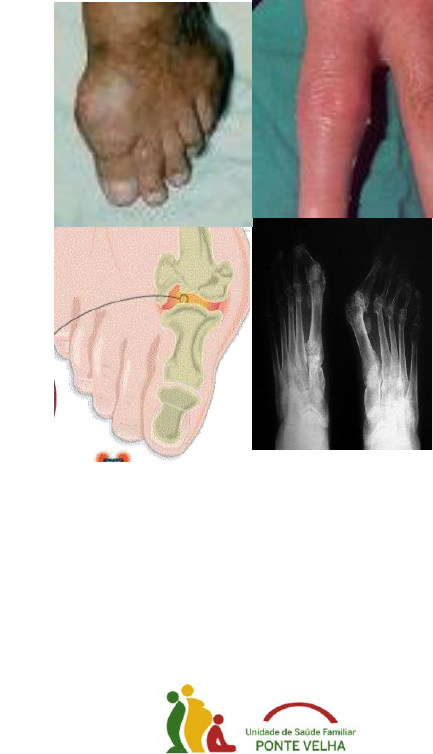

<p>Gota – Regime Alimentar</p><p>Alimentos Aconselhados:</p><p> Carne: vaca, galinha, carneiro, pato (sempre</p><p>limpa de peles e gorduras visíveis antes de</p><p>cozinhada)</p><p> Peixe: carapau, bacalhau (bem demolhado),</p><p>pescada, cachucho, pargo, corvina,</p><p>salmonetes</p><p> Hortaliça: alface, cenoura, feijão verde,</p><p>nabiças, grelos, nabos, alho-francês, couve</p><p>lombarda, agriões</p><p> Fruta (madura): maçã, pêra, banana, laranja,</p><p>pêssego, melão, melancia, figos</p><p> Bebidas: água, chás frescos, leite magro, se</p><p>não existirem outras contra-indicações pode</p><p>beber ½ a 1 copo de vinho às refeições</p><p>principais</p><p> Vários: arroz, massa, pão, batata, ovos, azeite,</p><p>queijo fresco, iogurte</p><p>Alimentos Desaconselhados:</p><p> Carne: animais jovens (borrego, cabrito, frango,</p><p>vitela), ou de caça (lebre, perdiz), porco,</p><p>chispe, presunto, produtos de salsicharia</p><p> Peixe: lulas, chocos, sardinha, sável, tainha,</p><p>peixe-espada, mariscos</p><p> Hortaliça: ervilhas, favas, espargos, espinafres</p><p> Fruta: ananás, cereja, ginja, limão, nêsperas</p><p> Bebidas: cerveja, aguardente, brandy,</p><p>conhaque, champagne, whisky, gin, vinho do</p><p>Porto, licores</p><p> Vários: azeitonas, feijão seco, grão, conservas,</p><p>chocolate, mel, queijo gordo curado</p><p>Alimentos não incluídos devem ser consumidos</p><p>com moderação</p><p>Conselhos Gerais</p><p>Embora os medicamentos prescritos pelo seu</p><p>médico sejam eficazes na redução dos níveis de</p><p>ácido úrico, existem medidas que poderão ajudá-</p><p>lo(a) a controlar os seus níveis de ácido úrico e</p><p>contribuirão para o(a) manter assintomático.</p><p>Evite o jejum prolongado</p><p>Controle o peso</p><p>(O excesso de peso e a obesidade aumentam a</p><p>probabilidade de crises)</p><p>Trate a Hipertensão Arterial</p><p>Trate a Dislipidemia</p><p>(colesterol e triglicerídeos elevados)</p><p>Dieta:</p><p> Moderação no consumo de alimentos ricos em</p><p>purinas (carne de animais jovens, caça,</p><p>vísceras, marisco)</p><p> Diminuir a ingestão de bebidas alcoólicas</p><p> Reduzir o conteúdo de gordura da dieta</p><p> Beber 1,5 a 2 litros de água, diariamente</p><p>Evite actividades que impliquem traumatismos</p><p>repetidos</p><p>Avise sempre o médico que tem o ácido úrico</p><p>elevado e qual a medicação que está a fazer</p><p>Realizado por Sónia Ferreira</p><p>Interna de MGF</p><p>GOTA</p><p>CENTRO DE SAÚDE DE SANTO TIRSO</p><p>Gota – doença caracterizada pela elevação do</p><p>ácido úrico no sangue e por surtos de inflamação</p><p>articular (artrite aguda), devidos ao depósito de</p><p>cristais de ácido úrico nas articulações.</p><p>Sintomas:</p><p> Dor articular intensa,</p><p>lancinante</p><p> Tumefacção, calor, e</p><p>rubor na área</p><p>afectada.</p><p>Articulações que podem ser atingidas:</p><p> Articulação metatarso-falângica do dedo</p><p>grande do pé (é a localização mais frequente)</p><p> Outras:</p><p> Calcanhar</p><p> Joelhos</p><p> Cotovelos</p><p> Punho</p><p> Dedos das mãos ou pés</p><p> As crises de Gota são, quase sempre</p><p>monoarticulares, isto é, atingem apenas uma</p><p>articulação.</p><p>As crises agudas de Gota</p><p> Surgem subitamente</p><p> O seu início é, na maior parte das vezes,</p><p>nocturno</p><p> São limitadas, isto é, sem tratamento, duram 1</p><p>a 2 semanas, após o que ocorre resolução</p><p>completa</p><p> São separadas por intervalos totalmente livres</p><p>de queixas, dando ao doente uma falsa</p><p>sensação de cura.</p><p>Factores precipitantes das crises:</p><p> Erros alimentares com ingestão excessiva de</p><p>carne, em particular de carne de porco, e de</p><p>bebidas alcoólicas</p><p> Emoções</p><p> Grandes esforços físicos, traumatismos</p><p> Intervenções cirúrgicas</p><p> Doenças infecciosas</p><p> Alguns medicamentos</p><p>Tratamento:</p><p>É diferente na crise aguda e nos períodos entre as</p><p>crises.</p><p>Durante a crise aguda:</p><p> Faça repouso</p><p> Coloque frio sobre a articulação afectada (saco</p><p>de água fria com algumas pedras de gelo)</p><p> Tome os medicamentos receitados pelo seu</p><p>médico pois estes diminuem a dor e combatem</p><p>a inflamação</p><p> Outras medidas:</p><p> Refeições ligeiras à base de vegetais, frutos</p><p>e leite.</p><p> Pode ingerir hidratos de carbono</p><p>(farináceos)</p><p> Evite a ingestão de proteínas e gorduras</p><p> Proibida a ingestão de bebidas alcoólicas</p><p>Entre as crises:</p><p> Tome sempre os medicamentos receitados pelo</p><p>seu médico, os quais são para manter toda a</p><p>vida.</p><p> Mantenha medidas dietéticas adequadas a um</p><p>estilo de vida saudável e adaptadas à sua</p><p>doença</p>